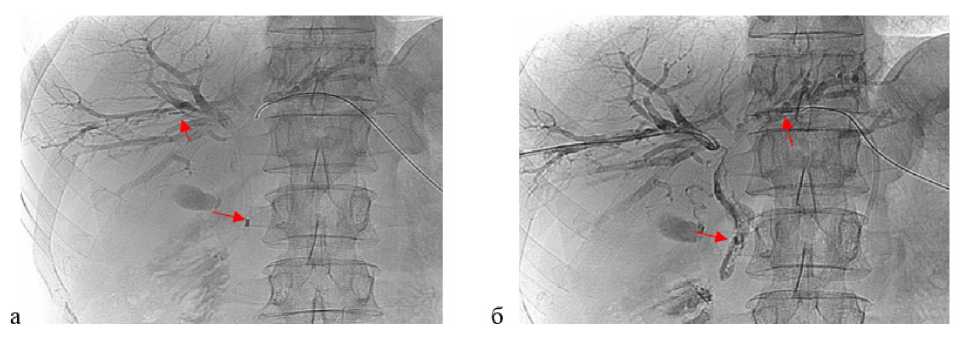

Рис. 1. Видеоассистированная внутрипротоковая щипковая биопсия под рентгеноскопическим контролем. а — рентгенограмма: ультратонкий эндоскоп установлен в месте выявленной опухоли на уровне конфлюенса общего печеночного протока; б — рентгенограмма: прицельная щипковая внутрипротоковая биопсия опухоли общего печеночного протока с использованием биопсийных щипцов

Рис. 2. Внутрипротоковая фотодинамическая терапия под рентгеноскопическим контролем. а — рентгенограмма: катетер с цилиндрическим диффузором заведен через правый долевой проток и расположен непосредственно на уровне опухоли, между дистальной и проксимальной рентгеноконтрастными метками (стрелки); б — рентгенограмма: катетер с цилиндрическим диффузором заведен через левый долевой проток и расположен непосредственно на уровне опухоли, между дистальной и проксимальной рентгеноконтрастными метками (стрелки)